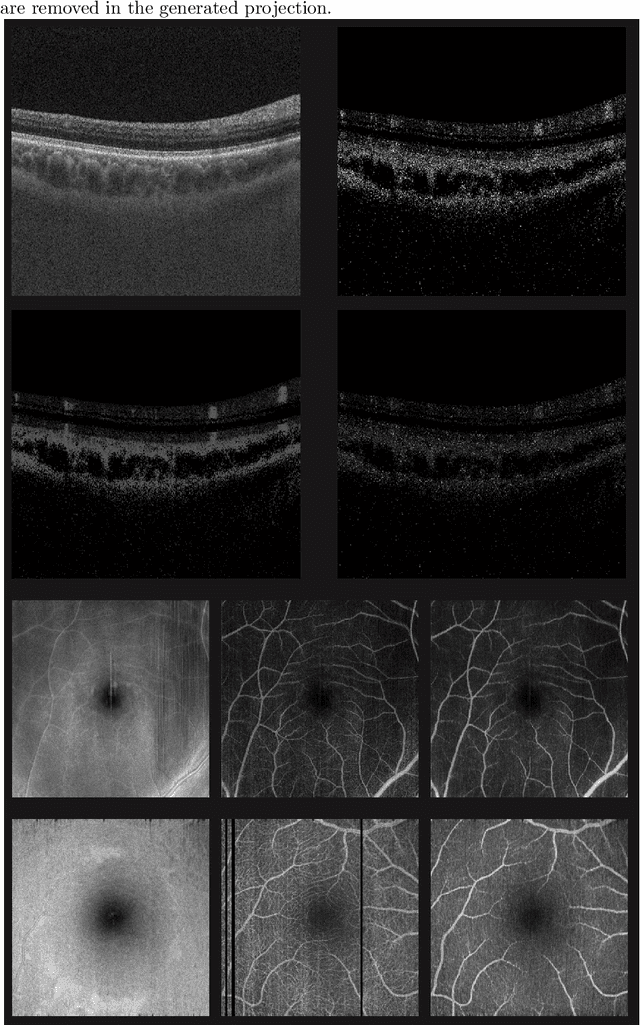

Abstract:Optical coherence tomography angiography (OCTA) is a novel and clinically promising imaging modality to image retinal and sub-retinal vasculature. Based on repeated optical coherence tomography (OCT) scans, intensity changes are observed over time and used to compute OCTA image data. OCTA data are prone to noise and artifacts caused by variations in flow speed and patient movement. We propose a novel iterative maximum a posteriori signal recovery algorithm in order to generate OCTA volumes with reduced noise and increased image quality. This algorithm is based on previous work on probabilistic OCTA signal models and maximum likelihood estimates. Reconstruction results using total variation minimization and wavelet shrinkage for regularization were compared against an OCTA ground truth volume, merged from six co-registered single OCTA volumes. The results show a significant improvement in peak signal-to-noise ratio and structural similarity. The presented algorithm brings together OCTA image generation and Bayesian statistics and can be developed into new OCTA image generation and denoising algorithms.

Abstract:Eye movements, blinking and other motion during the acquisition of optical coherence tomography (OCT) can lead to artifacts, when processed to OCT angiography (OCTA) images. Affected scans emerge as high intensity (white) or missing (black) regions, resulting in lost information. The aim of this research is to fill these gaps using a deep generative model for OCT to OCTA image translation relying on a single intact OCT scan. Therefore, a U-Net is trained to extract the angiographic information from OCT patches. At inference, a detection algorithm finds outlier OCTA scans based on their surroundings, which are then replaced by the trained network. We show that generative models can augment the missing scans. The augmented volumes could then be used for 3-D segmentation or increase the diagnostic value.

Abstract:Optical coherence tomography (OCT) enables high-resolution and non-invasive 3D imaging of the human retina but is inherently impaired by speckle noise. This paper introduces a spatio-temporal denoising algorithm for OCT data on a B-scan level using a novel quantile sparse image (QuaSI) prior. To remove speckle noise while preserving image structures of diagnostic relevance, we implement our QuaSI prior via median filter regularization coupled with a Huber data fidelity model in a variational approach. For efficient energy minimization, we develop an alternating direction method of multipliers (ADMM) scheme using a linearization of median filtering. Our spatio-temporal method can handle both, denoising of single B-scans and temporally consecutive B-scans, to gain volumetric OCT data with enhanced signal-to-noise ratio. Our algorithm based on 4 B-scans only achieved comparable performance to averaging 13 B-scans and outperformed other current denoising methods.